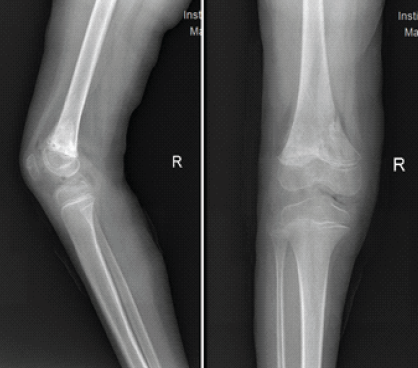

He was followed up in the outpatient department at 2 weeks, 6 weeks, 2 months, 3 months, 6 months, and 1 year postoperatively. At the end of 2 months, the K-wires and slab were removed with gentle knee bending exercises. At 3 months, a repeat X-ray was obtained, which showed satisfactory union (Fig. 6).

Figure 6: X-ray right knee anteroposterior and lateral view at the end of 3 months.